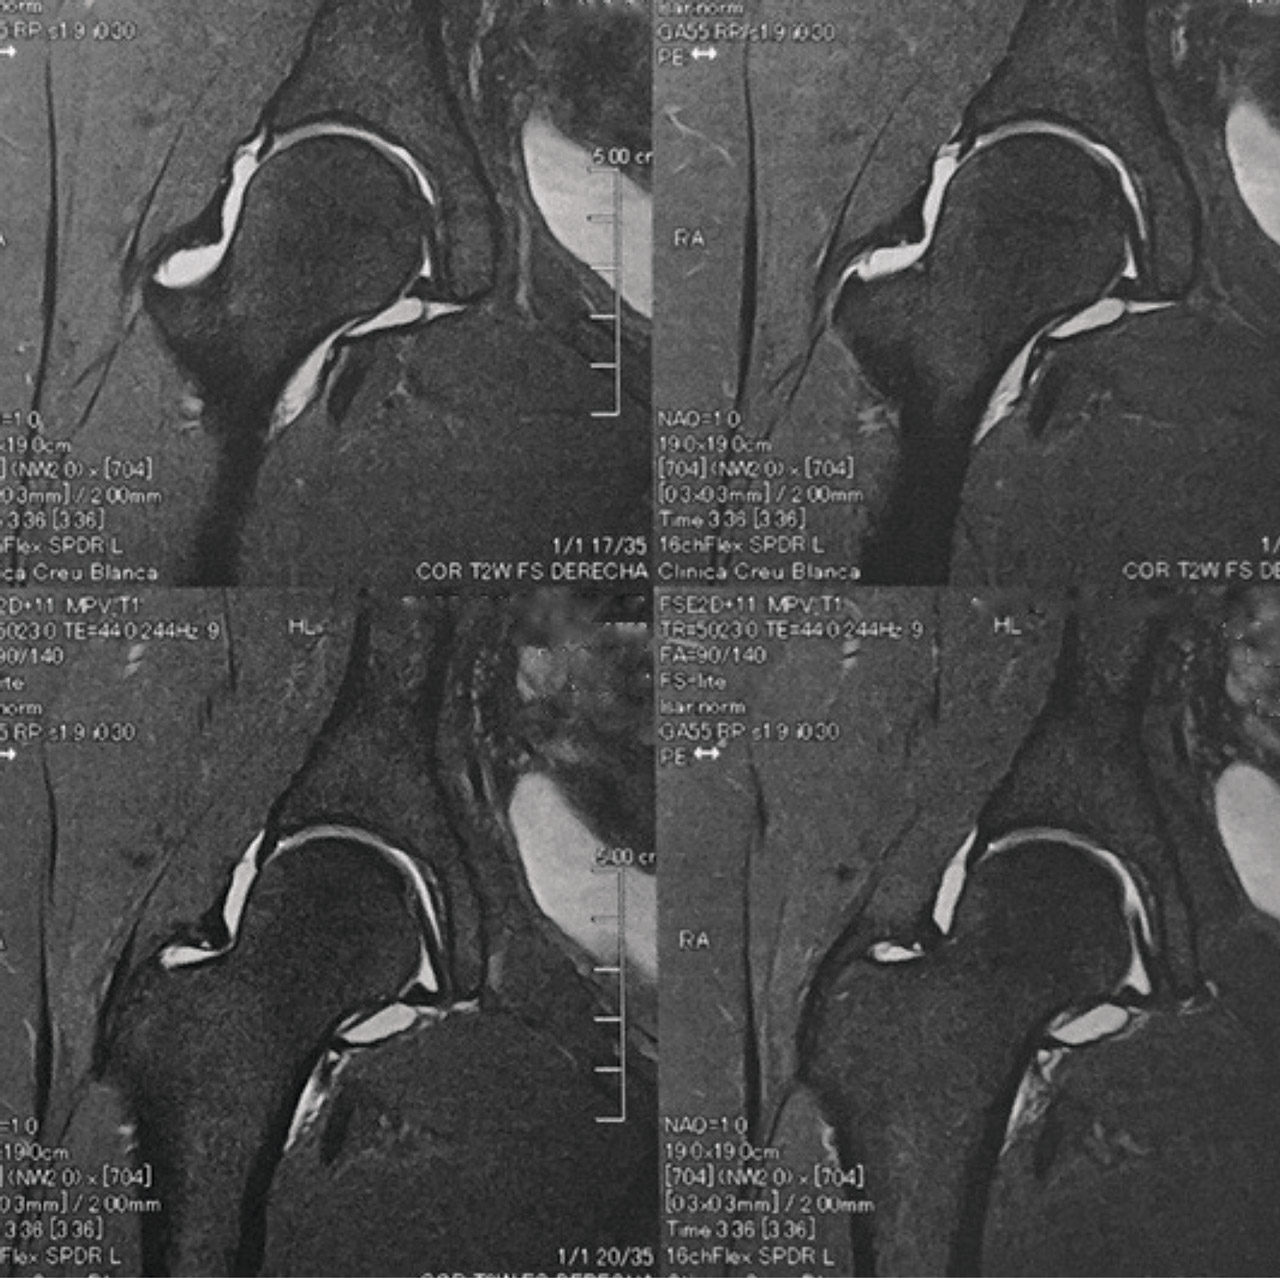

Las pruebas de imagen no muestran alteraciones en forma de deformidad de tipo CAM ni PINCER (tanto en radiografías como en resonancia). El ángulo alfa en la proyección axial era de 38,2° y el ángulo Wiberg de 34,5° (Figura 5). Asimismo, el estudio mediante artrorresonancia no evidenció lesiones de labrum ni deformidades del tipo AFA (Figura 6).

Figura 6. Las imágenes de resonancia magnética mostraban ausencia de lesiones de labrum y de deformidades óseas de tipo pinzamiento femoroacetabular.